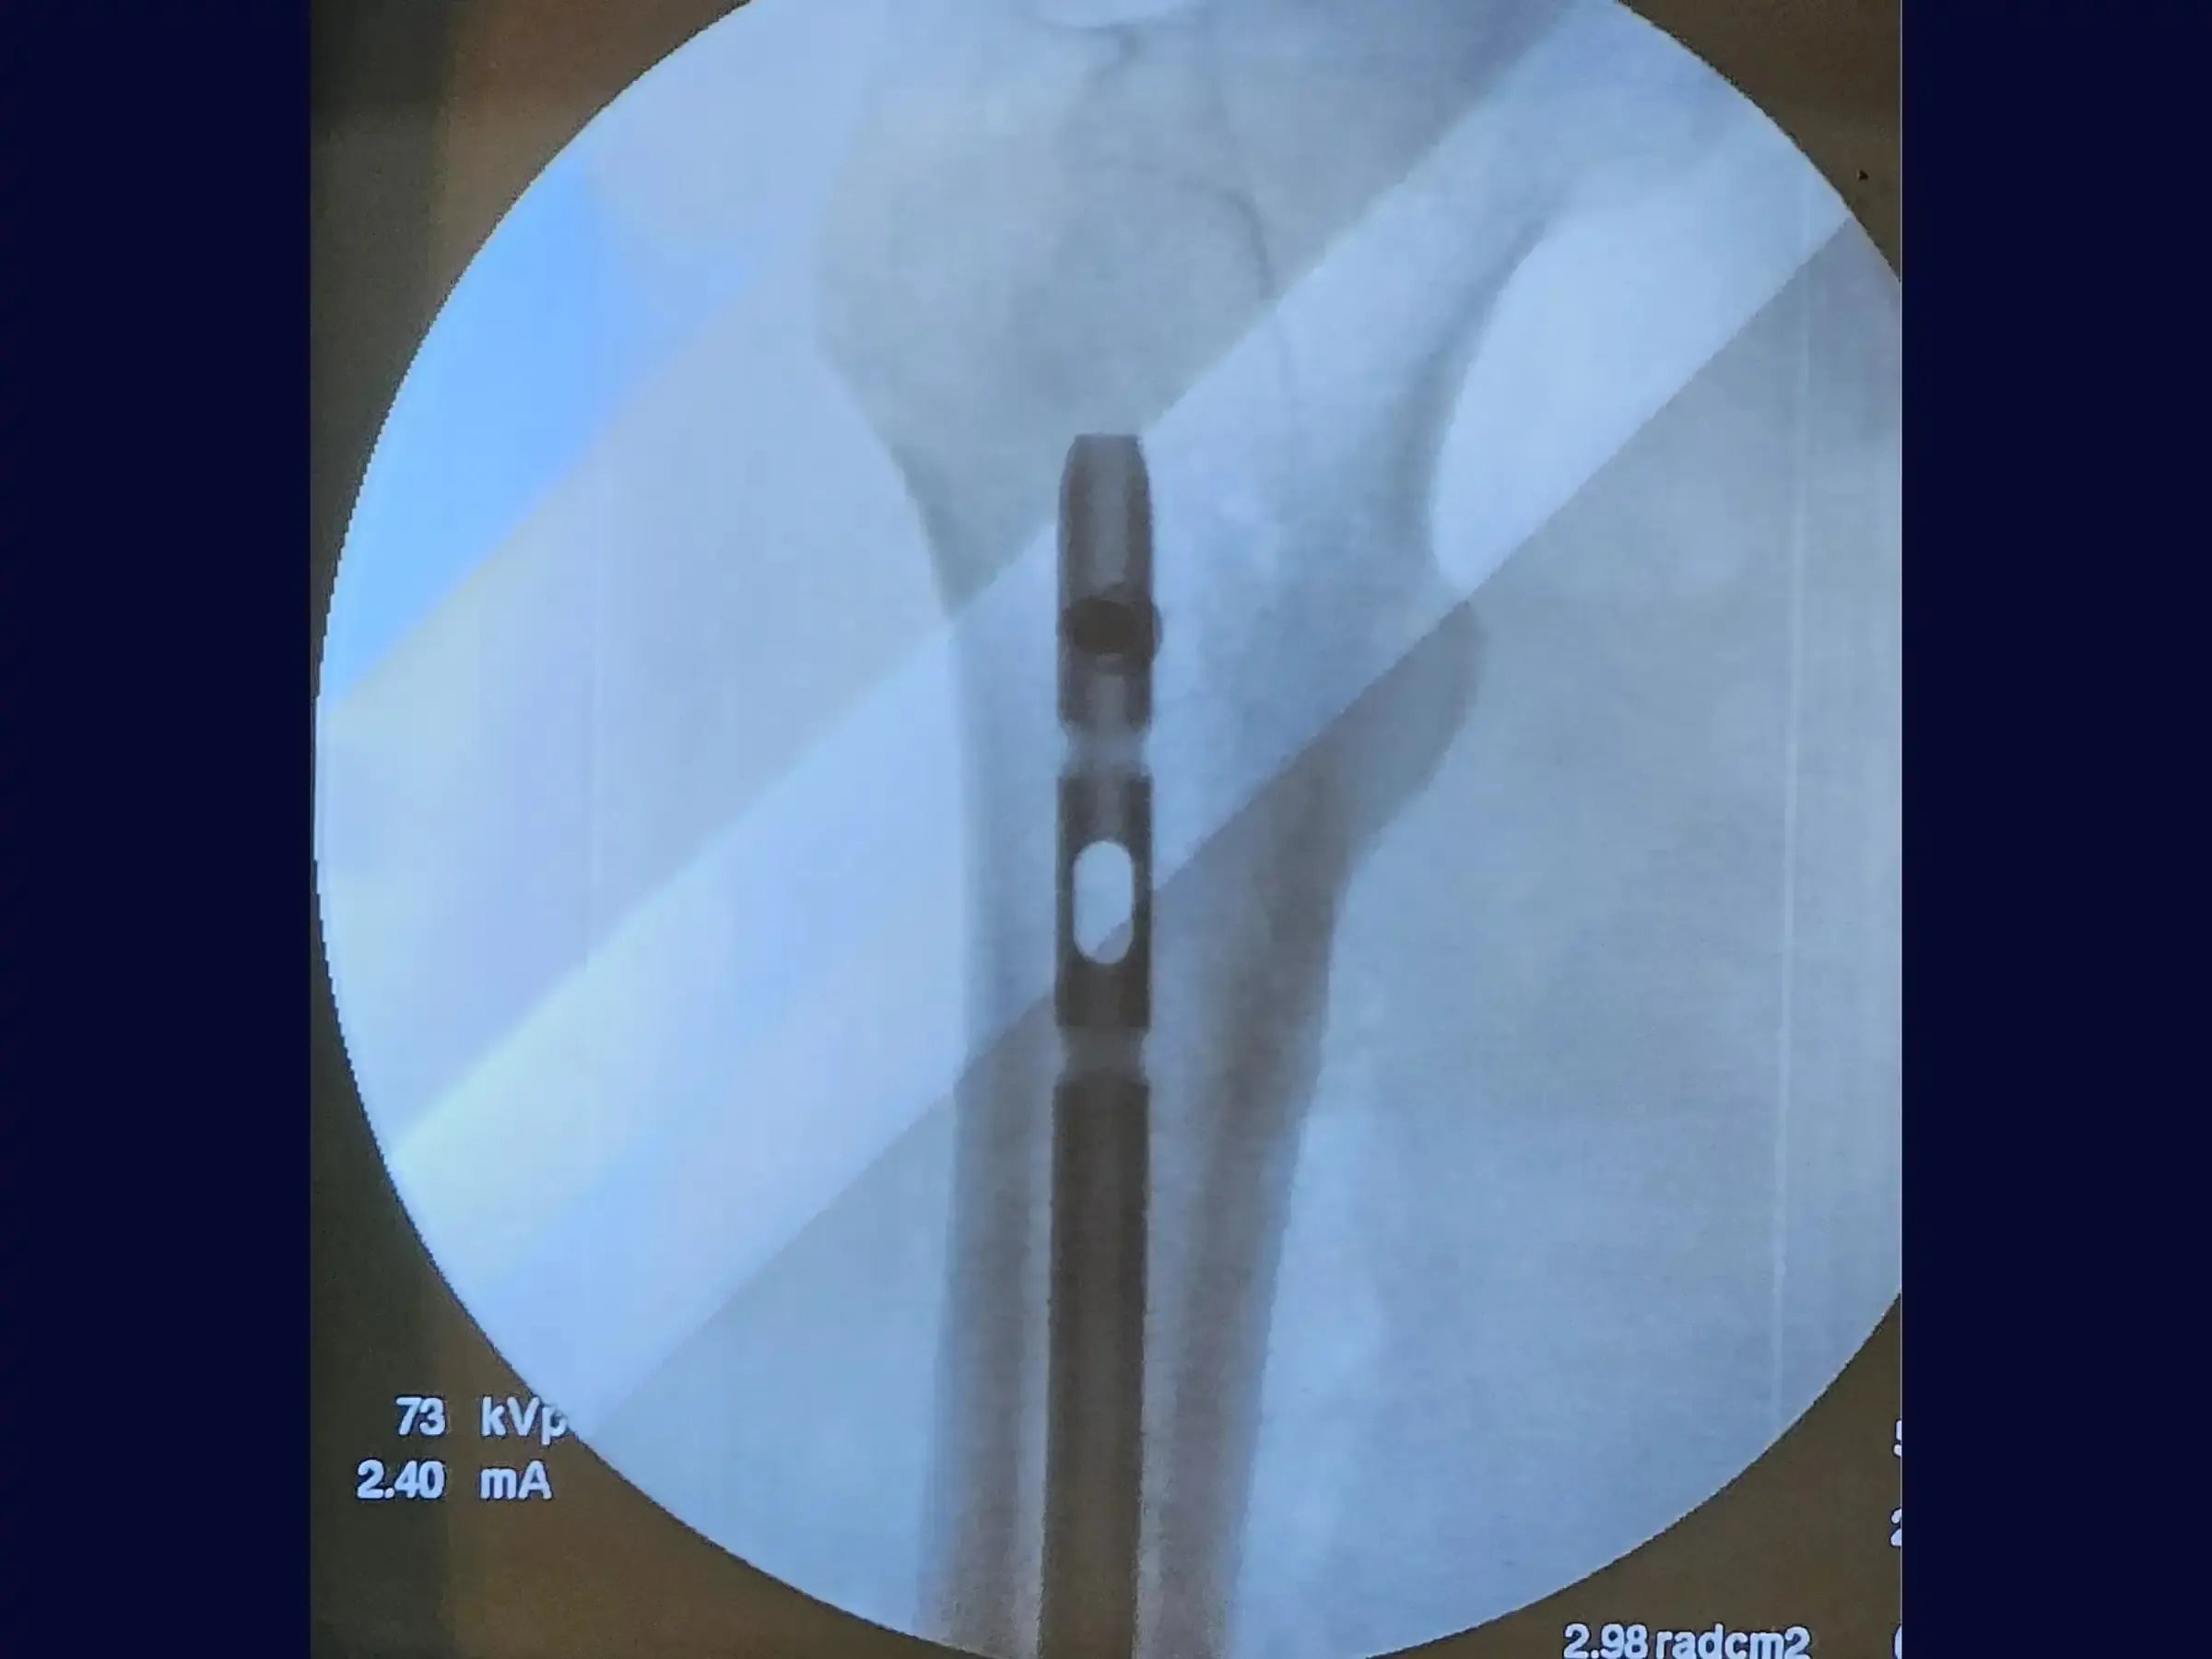

- Introdução da Haste Intramedular Retrógrada: Aprenda a introduzir a haste de forma retrógrada com conferência constante das imagens fluoroscópicas, garantindo que a extremidade da haste direcionada ao quadril ultrapasse o pequeno trocânter para evitar estresse e risco de fratura subtrocantérica.

- Bloqueio Proximal Minimamente Invasivo: Realize o bloqueio proximal sob fluoroscopia, com acesso minimamente invasivo, assegurando a conferência do perfil através da rotação da perna para certificar o tamanho correto do bloqueio, mesmo com grande massa muscular.

- Resultados Otimizados: Obtenha resultados cirúrgicos onde a haste está posicionada acima do pequeno trocânter e seguindo a linha de Blumensatt, sem proeminências no joelho, permitindo certa mobilidade no pós-operatório.